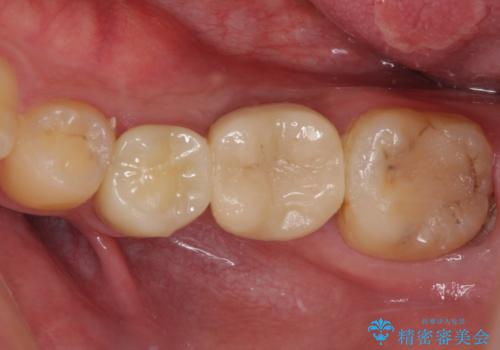

セラミッククラウンによる奥歯のむし歯治療

- 奥歯がしみて痛いとのことで来院された患者様です。

既に複数箇所の修復が行われていたため、オールセラミッククラウンにて補綴をすることとしました。

以前装着した修復物が不適であり、歯肉が腫れていましたが、仮歯を装着したことで腫れは解消されました。

歯の痛みだけでなく、歯肉の腫れも改善され、患者様には大変満足していただきました。